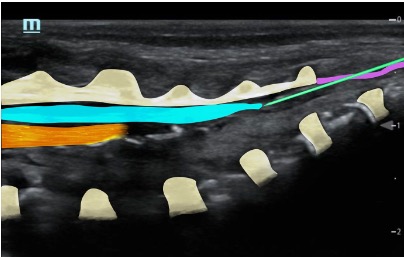

Perform saline test à Confirm position (saline expands the epidural space and pushes the dura more anteriorly)

Slowly inject LA and observe spread (aspirate repeatedly)

Track the  LA spread by sliding the probe cranially (probe positioned paramedian longitudinally); ensure the appropriate level is reached for the intended operation